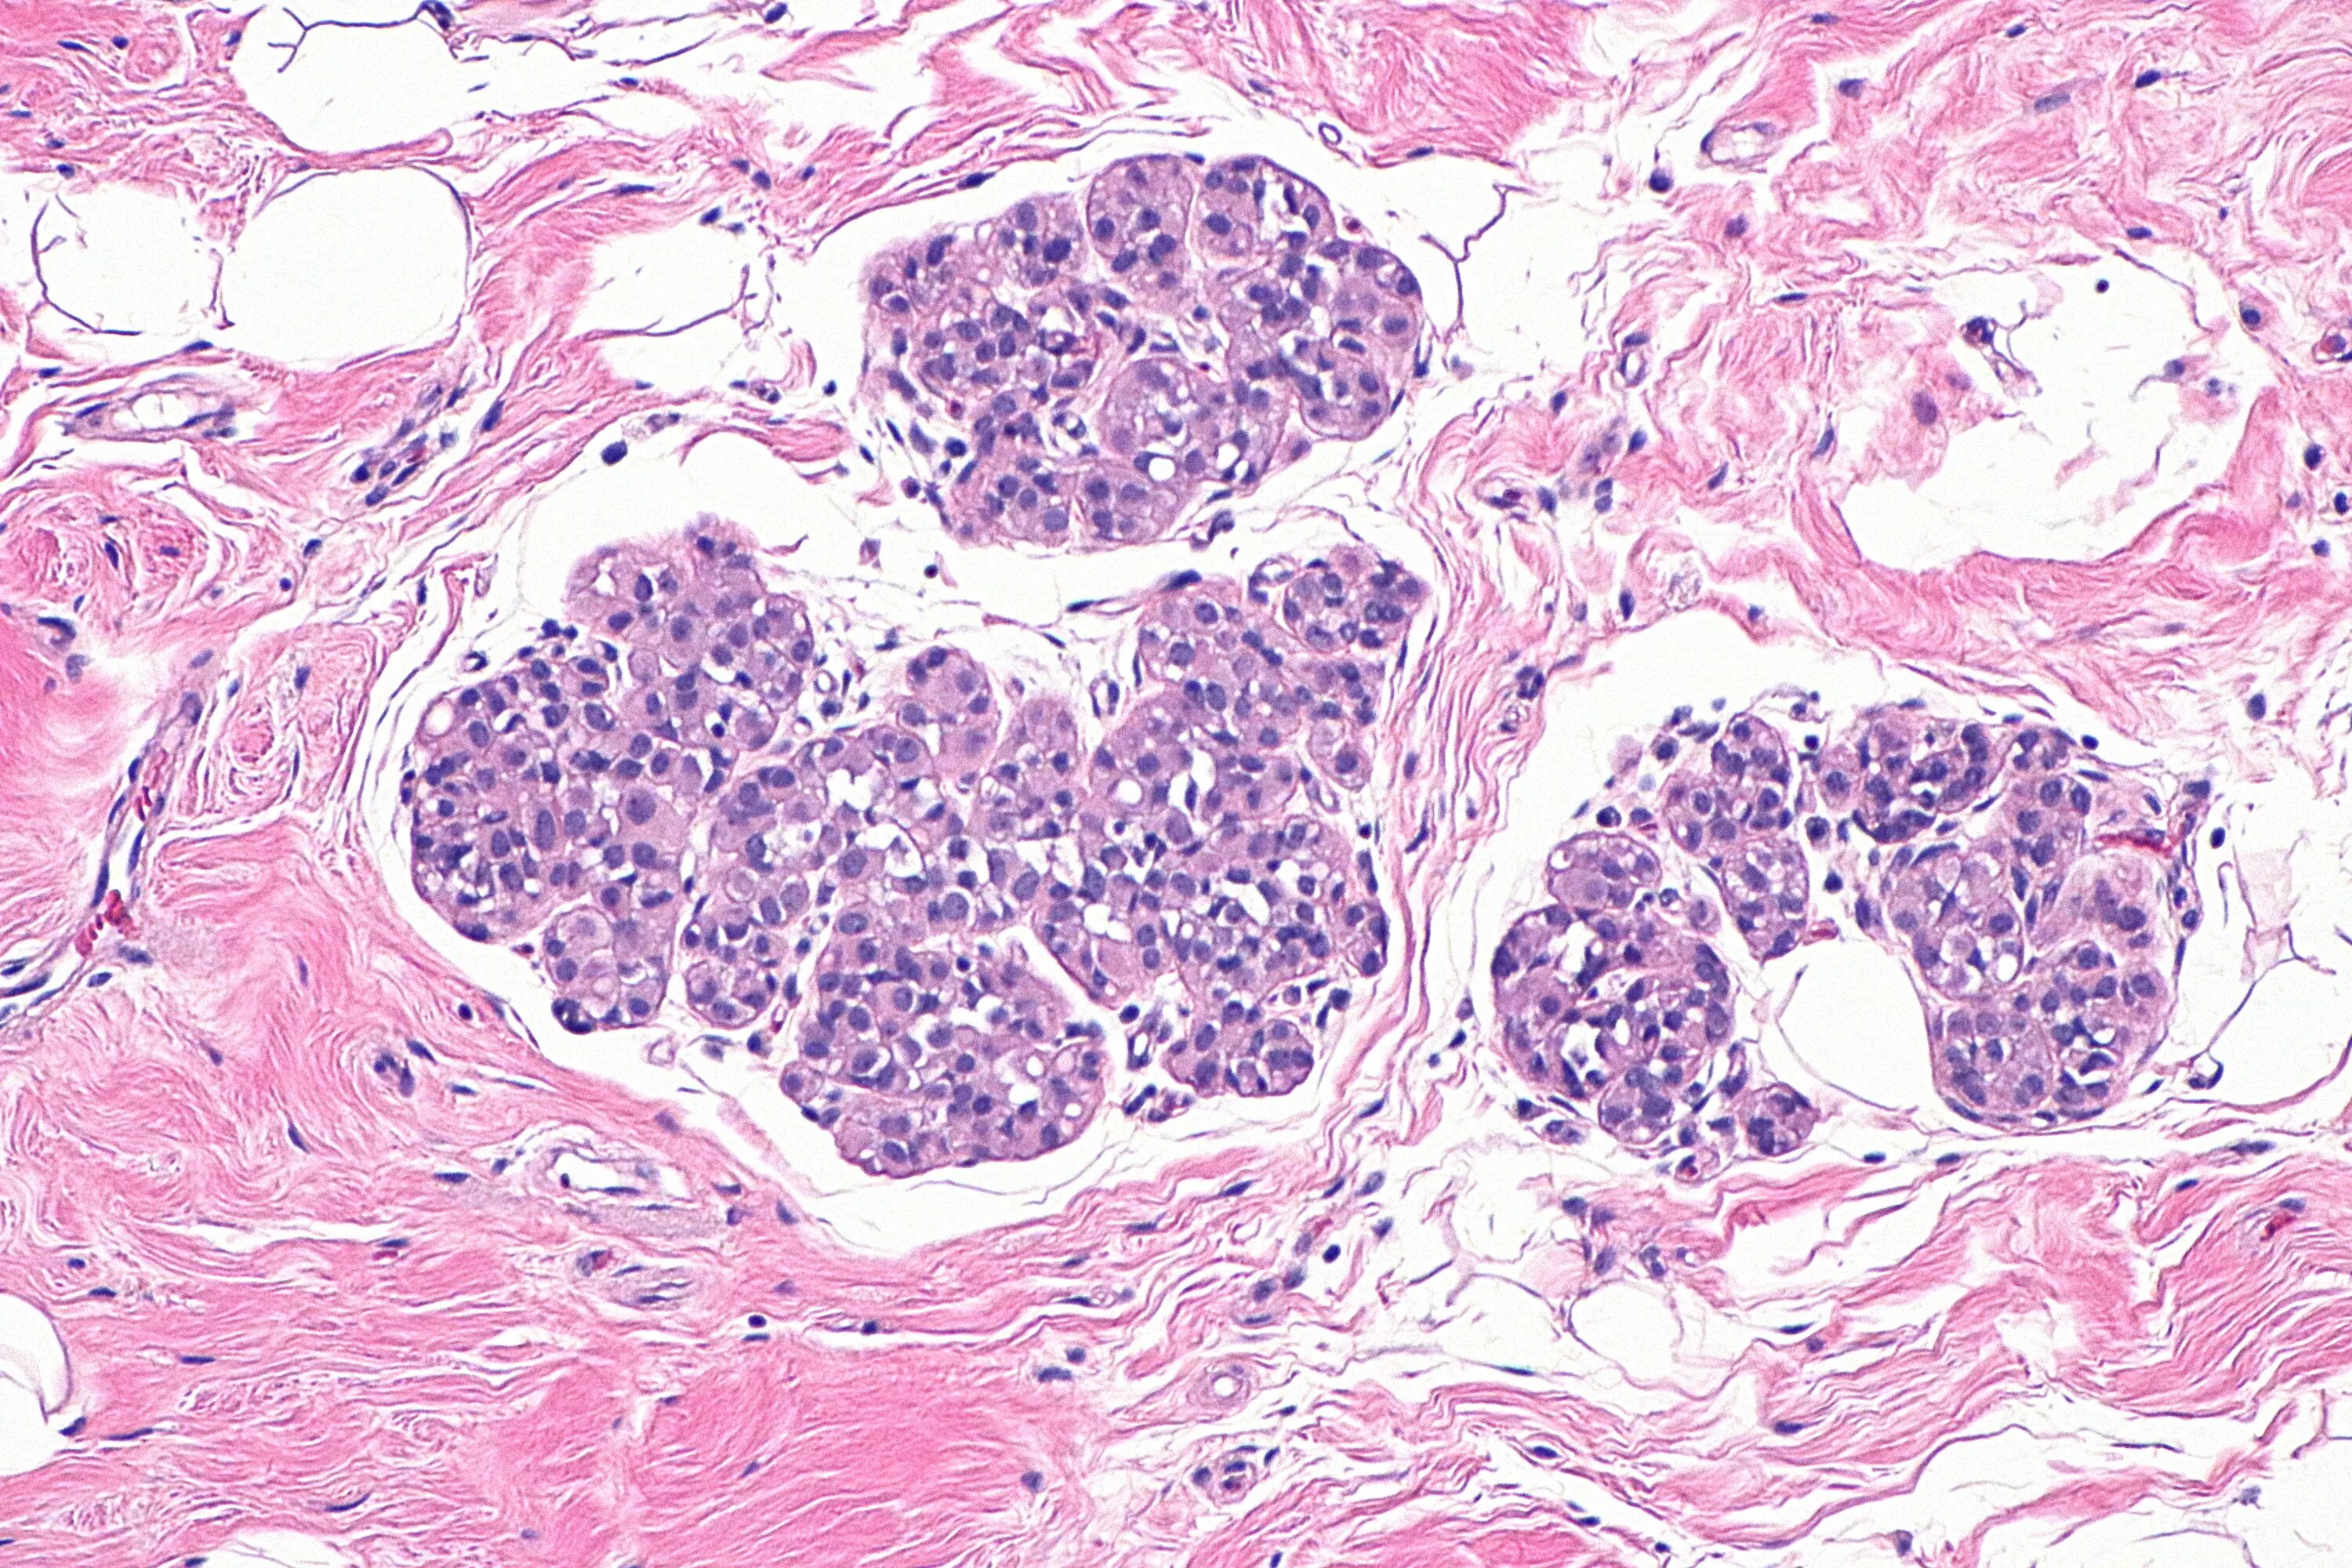

Фиброаденома гистология